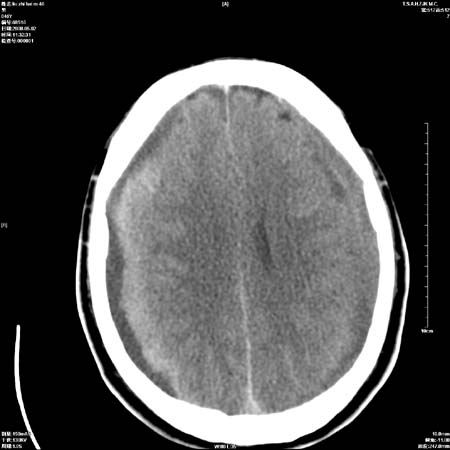

男性   46岁   头晕头痛一周    无任何外伤史    有高血压病史

亚急性硬膜下血肿

考虑双侧慢性硬膜下出血

支持双侧慢性硬膜下血肿。

应该是亚急性(3天——3周)硬膜下出血

亚急性硬膜下血肿;典型。